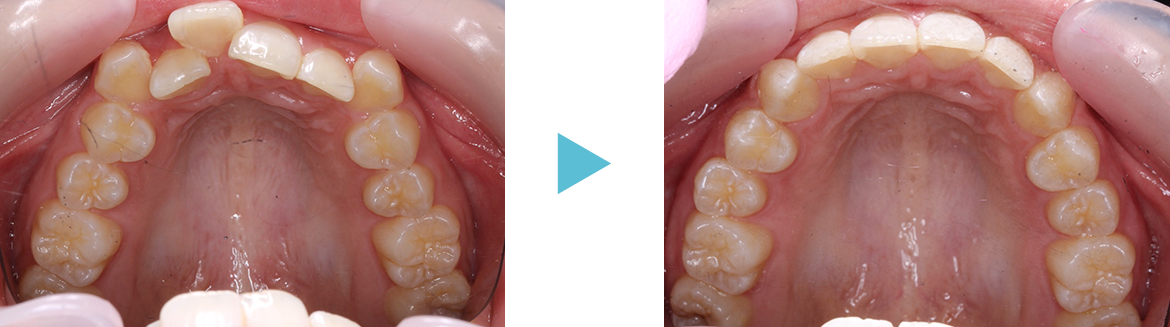

歯並びが混み合っている原因は歯の大きさに対して歯列(顎の大きさ)が小さいことが多いです。

硬いものをよく噛んでいれば顎が成長するのでしょうが、柔らかいものを食べている私たちは顎が小さくなっています。そこで歯列を大きくする拡大装置を使って歯列全体を大きくして永久歯が綺麗に並ぶように治療します。